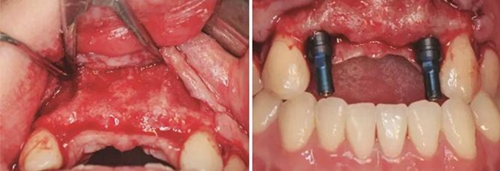

(4)2015年3月—2015年12月:早期修復(fù)伴軟組織誘導(dǎo)成形對(duì)患者制取開窗印模后,使用橋用金屬臨時(shí)基臺(tái),制作聚甲基丙烯酸甲酯(PMMA,登士柏公司,德國(guó))經(jīng)CAD/CAM切削的臨時(shí)修復(fù)橋體,戴入臨時(shí)修復(fù)體對(duì)牙齦軟組織進(jìn)行誘導(dǎo)成形,采用動(dòng)態(tài)加壓技術(shù),最初緩慢戴入臨時(shí)修復(fù)體,撐開牙齦軟組織袖口,擠壓粘膜,粘膜受到擠壓后缺血變白,10min內(nèi)可恢復(fù)為粉紅色。臨時(shí)修復(fù)體為縱向螺絲固位,便于拆卸調(diào)改形態(tài),囑患者勿用臨時(shí)修復(fù)體咬物,注意口腔衛(wèi)生,用牙線或沖牙器等將種植體周圍清潔干凈,每月進(jìn)行復(fù)查,不斷調(diào)改臨時(shí)冠的穿齦形態(tài),讓出軟組織生長(zhǎng)空間,直至誘導(dǎo)牙齦形成類似于天然牙的穿齦袖口形態(tài)。其中在早期修復(fù)3月時(shí),通過打開修復(fù)體間的三角間隙,以讓出齦乳頭生長(zhǎng)的空間;在早期修復(fù)7月時(shí)對(duì)22位點(diǎn)唇側(cè)牙齦根方的軟組織增生物進(jìn)行刮除并縫合,同時(shí)將修復(fù)體的橋體部位調(diào)磨成卵圓形的蓋嵴部并高度拋光,以獲得良好的橋體部軟組織形態(tài),形成健康、連續(xù)且協(xié)調(diào)的軟組織輪廓。

圖19 早期修復(fù)1月 圖20 早期修復(fù)2月

圖21 早期修復(fù)3月 圖22 早期修復(fù)3月打開三角間隙

圖23 早期修復(fù)4月 圖24 早期修復(fù)7月切除軟組織增生后

圖25 早期修復(fù)7月調(diào)改橋體部形態(tài)為卵圓形并高度拋光 圖26 早期修復(fù)8月